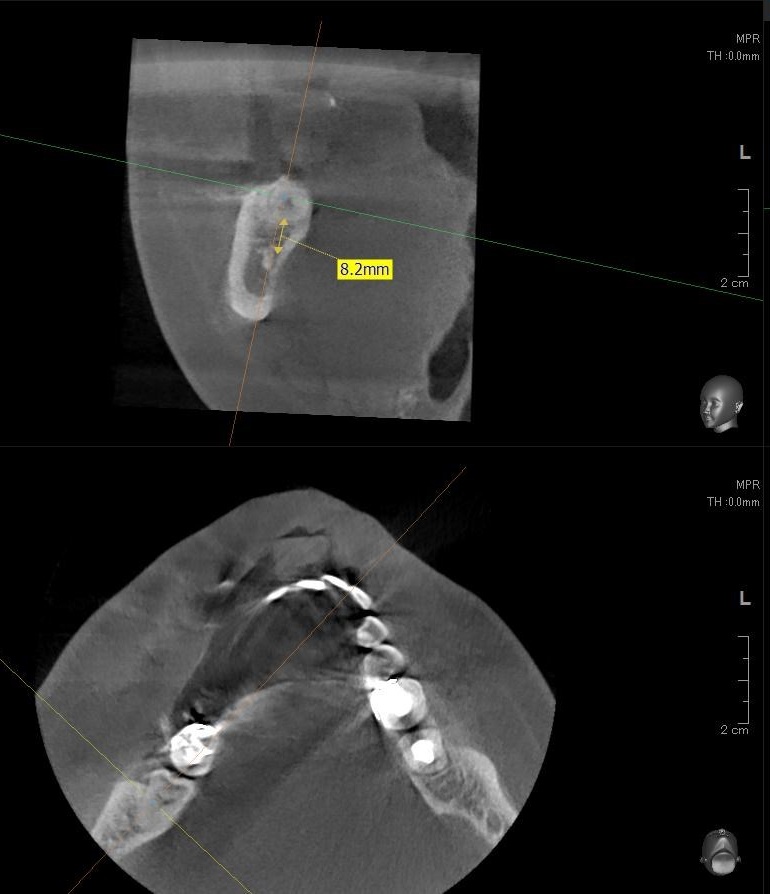

さらに、下顎の親知らずは下歯槽神経に非常に近いところに生えている場合もあるため、CTも撮影し詳しい解析を行います。

親知らずが生えている位置が、神経に近い、あるいは神経に当たっている場合は、大きな病院に紹介する場合もあります。

親知らずの根っこは下歯槽神経から近い距離にありますが、抜歯は可能との診断でした。